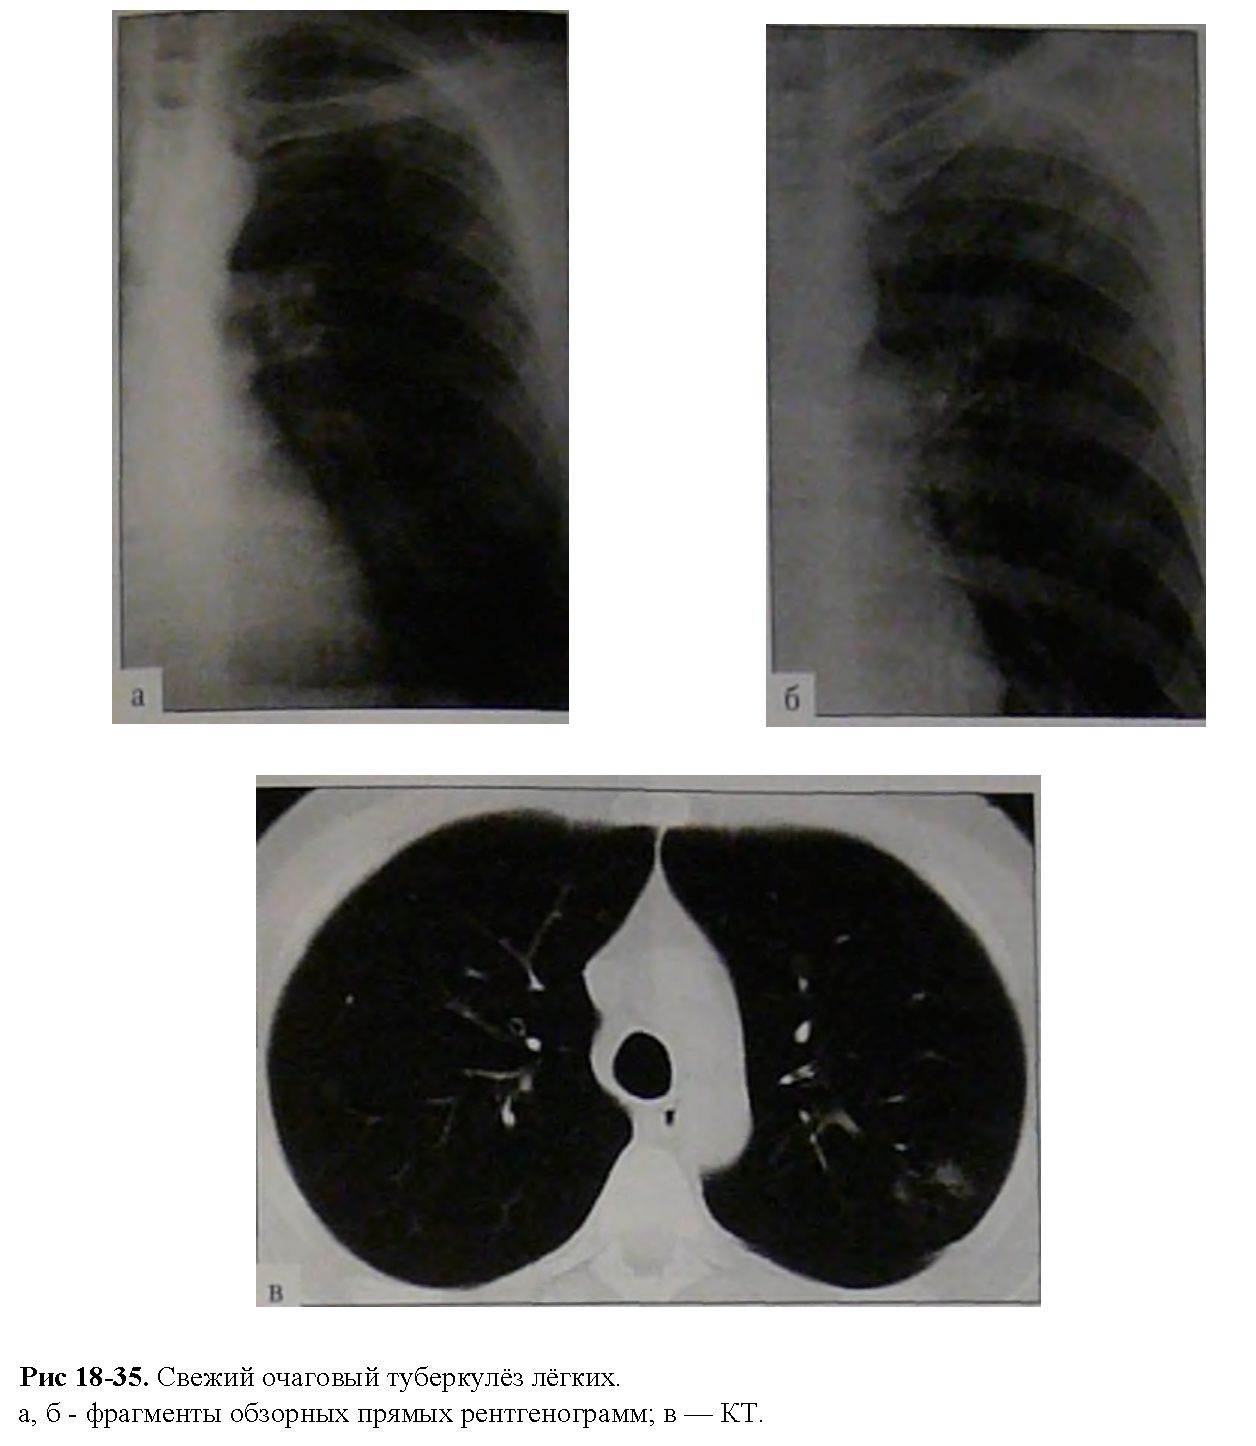

Снимок легких при туберкулезе является важным методом диагностики этого заболевания. На рентгеновских снимках можно увидеть изменения в легких, которые свойственны туберкулезу.

Очаговый туберкулез рентген

Очаговый туберкулёз ренген

Фиброзно очаговый туберкулез рентген

Фиброзно-очаговый туберкулез рентгенограмма

Фотографии снимков легких при туберкулезе

В данной статье представлены многочисленные фотографии снимков легких при туберкулезе, чтобы помочь вам понять, как выглядят изменения легких на рентгеновских снимках при этом заболевании.